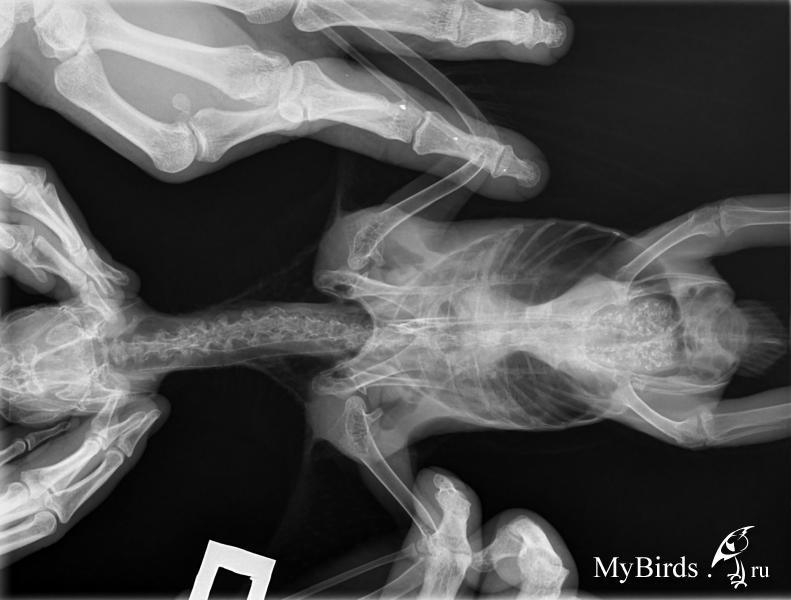

kuzub Опубликовано 23 ноября, 2013 Автор #61 Опубликовано 23 ноября, 2013 Наш Гриша вчера умер, у мужа на руках Мы сделали вскрытие в зоопарке, вот его результаты: 1) Почки в норме. 2)Цирроз печени. 3) Слипчивое воспаление печени и кишечника 4)Киста яичника. 5) Двустороннее воспаление лёгких. 6)Воздухоносные мешки полностью покрыты плотными слоистыми козеозными массами. Фото вскрытия прилагаю. Так же есть фото рентгена, на котором видно, что у Гришки проблемы с почками. По факту оказалось, что с почками всё хорошо, а печень и лёгкие в ужасном состоянии(((

Zosia Опубликовано 23 ноября, 2013 #70 Опубликовано 23 ноября, 2013 Откуда набор?Да очень просто.Птица контрабандная, Татьяна купила его в прошлом году, с рук. Птиц взрослый. Соответственно- все уже у него было в наличии.Просто в момент покупки еще в скрытой форме. как птиц привозят к нам- я знаю.Это страшно. В пути они получают все инфекции какие можно.два года назад, лето-осень 2011 года,на форуме появилась партия жако алохвостых (от 8 месяцев до 2 лет, по описанию), все с аспергиллезом, с гепатозами, с жуткими энтеритами.Умерло четверо,одного хозяйка вытащила вифендом,уколами.вливаниями и месячным отпуском за свой счет,один остался инвалидом. ВСЕ ОНИ ПОКУПАЛИСЬ В КРАСНОДАРЕ. Малыши умерли все... не хватило сил, сердечки были слабые и с токсикозом не справились. Маша ЭКВИ вела троих точно, у меня было двое, один вообще не дожил даже до первых анализов,умер через 5 (!) дней после покупки. Я уже говорила ранее, и повторю сейчас- жако (что бурики,что алохвостые)- самые "капризные" из среде-крупных и крупных попугаев. По обмену веществ (рахиты всех видов, подагры, артрозы солевые,нарушение фосфорно-кальциевого баланса), по подверженности грибковым заболеваниям и по тяжести их излечения (на них работает практически только вифенд,который стоит дорого), по иммунке во время линьки. Про психику же я вообще молчу. Чем выше интеллект у птицы- тем тяжелее с ней ДОЛГО жить... Те же амазоны,которые сравнимы с жако по условиям обитания в природе и по массе- гораздо,гораздо "крепче". И еще больнее,когда птица смотрит на тебя человеческими глазами, а ты помочь не можешь... и объяснить не можешь... И почки у него тоже были в хлам(хоть анатом и другое сказал, но я видела рентген).